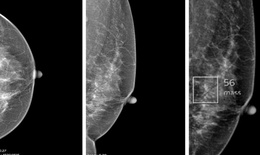

Phát hiện sớm ung thư vú nhờ công nghệ AI

Ung thư - 08/10/2025 12:02SKĐS - Ung thư vú đang ngày càng trẻ hóa. Nếu trước đây bệnh chủ yếu gặp ở phụ nữ trên 45 tuổi, thì nay nhiều ca được phát hiện ở độ tuổi 30–40, thậm chí dưới 30 tuổi. Tuy nhiên, ung thư vú có thể phát hiện sớm và điều trị hiệu quả.